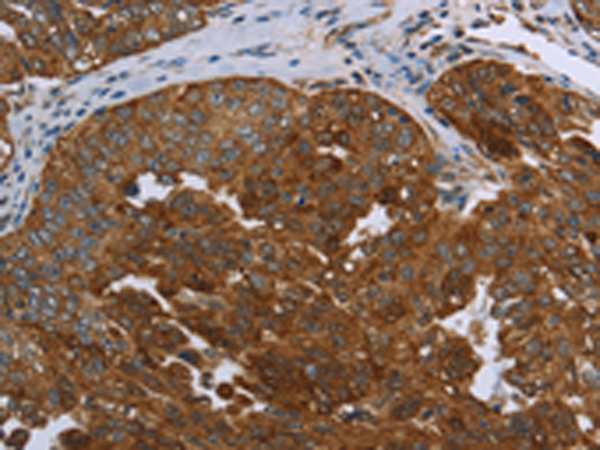

分类: 科研抗体货号: P00147别名: ANG3; ARP1; AngY; ANGPT3; UNQ162; dJ595C2.2应用: IHC反应种属: Human, Mouse